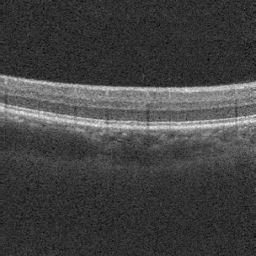

Optical coherence tomography angiography (OCTA) shows its great importance in imaging microvascular networks by providing accurate 3D imaging of blood vessels, but it relies upon specialized sensors and expensive devices. For this reason, previous works show the potential to translate the readily available 3D Optical Coherence Tomography (OCT) images into 3D OCTA images. However, existing OCTA translation methods directly learn the mapping from the OCT domain to the OCTA domain in continuous and infinite space with guidance from only a single view, i.e., the OCTA project map, resulting in suboptimal results. To this end, we propose the multi-view Tri-alignment framework for OCT to OCTA 3D image translation in discrete and finite space, named MuTri. In the first stage, we pre-train two vector-quantized variational auto-encoder (VQ- VAE) by reconstructing 3D OCT and 3D OCTA data, providing semantic prior for subsequent multi-view guidances. In the second stage, our multi-view tri-alignment facilitates another VQVAE model to learn the mapping from the OCT domain to the OCTA domain in discrete and finite space. Specifically, a contrastive-inspired semantic alignment is proposed to maximize the mutual information with the pre-trained models from OCT and OCTA views, to facilitate codebook learning. Meanwhile, a vessel structure alignment is proposed to minimize the structure discrepancy with the pre-trained models from the OCTA project map view, benefiting from learning the detailed vessel structure information. We also collect the first large-scale dataset, namely, OCTA2024, which contains a pair of OCT and OCTA volumes from 846 subjects.